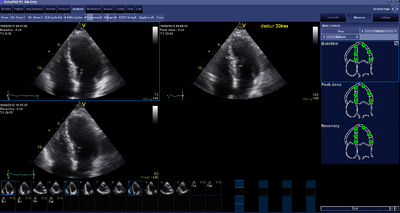

Advance is first made with the echo resting platelets: A PLAX, PSAX pm, AP4Ch and AP2Ch.

At maximum heart rate echo recordings are again made. Another PLAX, PSAX pm, AP4Ch and AP2Ch, are made exactly like the rest plates (otherwise do not compare the recordings with each other) that requires only routine of the sonographer. Then ensure that the heart rate is slow again.1